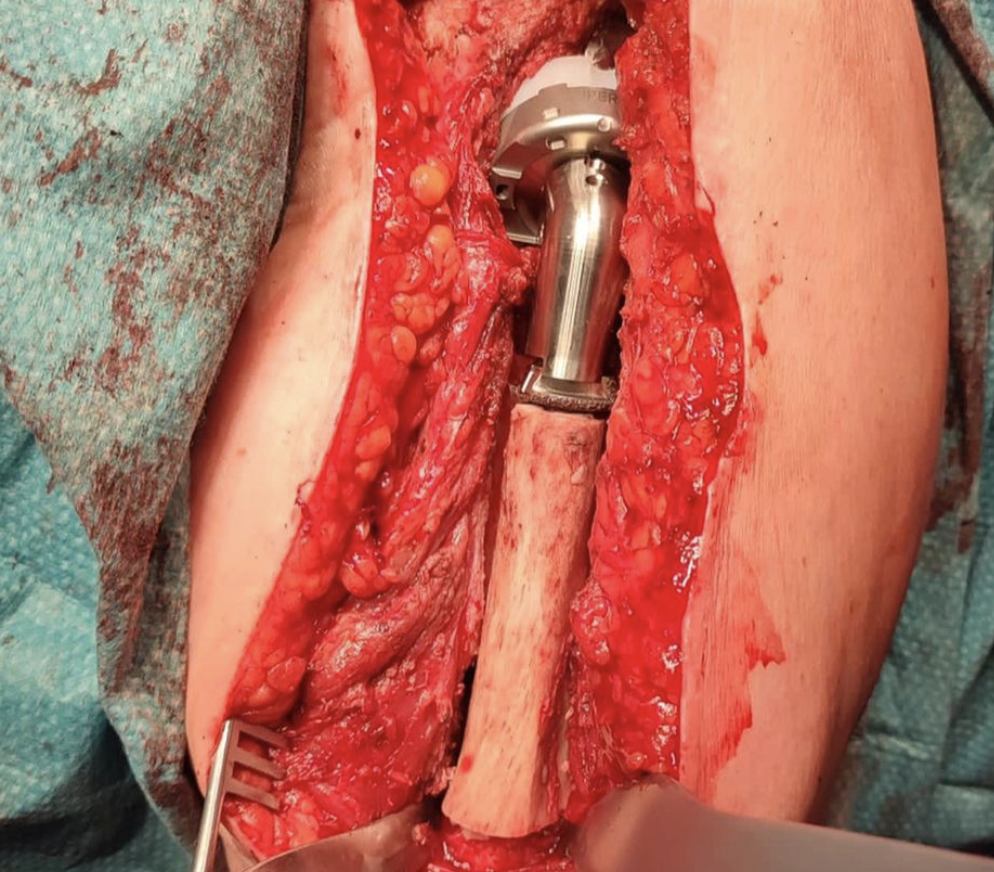

Condrosarcoma en húmero

Hoy me gustaría compartir el caso de una mujer de 72 años con un condrosarcoma G3 de humero izquierdo (imágenes 1,2),  a quien hace 1 año se le realizó una resección (imagen 3) y reconstrucción con la megaprótesis invertida Comprehensive SRS cementada de Zimmer Biomet. (imagen 4) Radiografía de control (5). A los 6 meses presenta un aflojamiento aséptico (imagen 6). Retiramos el componente humeral (imagen 7) y reconstruimos con un ALOINJERTO TELESCOPICO PRESSFIT (imagen 8) y un nuevo componente humeral mas corto (imagen 9) Radiografías de la reconstrucción AloProtésica (imagen 10)

Para poder ayudar a los pacientes con sarcomas debemos tener múltiples opciones reconstructivas, ya sea para el procedimiento inicial, como para las complicaciones que puedan surgir